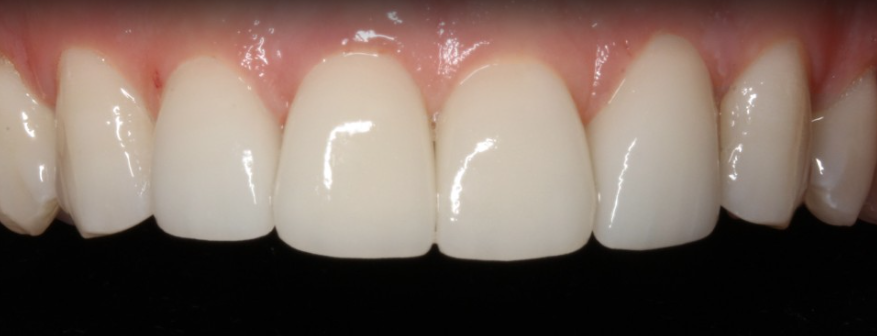

김현모 대표원장님께서 연구개발하신

무삭제라미네이트는 아주 얇은 0.1mm

두께로 치아와 유사한 색상과 모양으로

고객님들의 치아 모양에 맞춰

치아변색 고민을 해결해드리고 있습니다.

앞니 장인분들이 수제작으로 블랙필름을

제작하고 있습니다.

고객님들마다 얼굴 이미지에 맞는 치아가

있기 때문에 얼굴과 치아 디자인을 함께

고려하여 고객님들에게 어울릴만한

치아디자인도 함께 추천해 드리고,

고객님들이 원하시는 치아 모양에 대해서도

취향과 의견을 적극 반영하여

치아를 제작하고 있습니다.

앞니 장인이 직접 1:1 맞춤 수제작하는

블랙필름은 투명하게 자연치처럼

자연스러운 투명한 광택감이 돌기 때문에

인위적인 디자인보다 자연스럽게

디자인을 추구하고 있습니다.